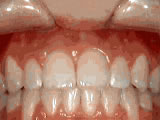

Missing lateral incisors

missing incisors after

After

This patient's lateral incisors were congenitally missing. She had braces for 20 months to move the teeth into their correct positions, then the missing teeth were replaced with bonded "Maryland" bridges.